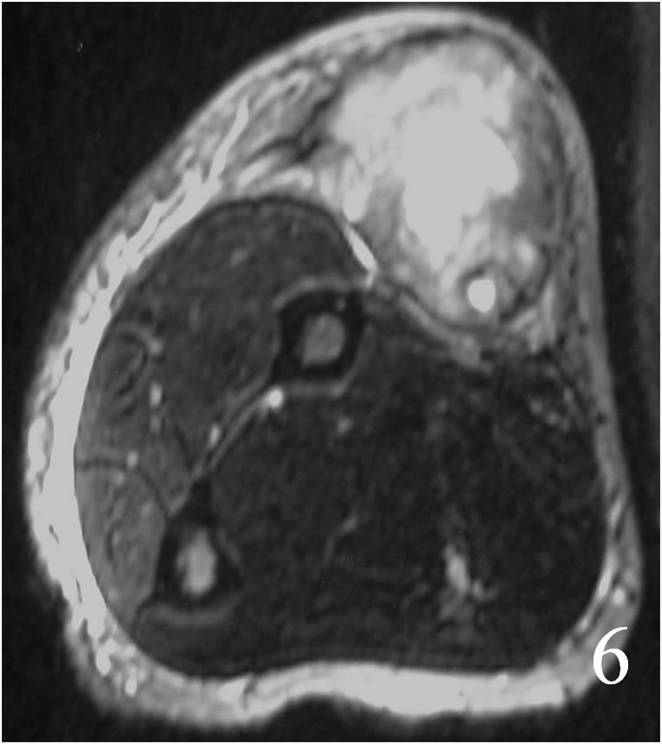

Large heterogeneous mass (Fig. 4, 5, 6)

Fig. 4 MRI of a leiomyosarcoma of the forearm shows a mass isointense to muscle on T1W image, heterogeneous on T2W (Fig. 5) and enhances with contrast T1W fat suppressed (Fig. 6)